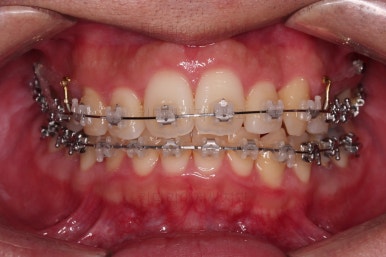

장치를 부착한 사진입니다.

이번 환자분이 부산앞니교정 선택하신 장치는 엠파워 클리어라고 하는 자가결찰(스스로 철사를 묶어주는 뚜껑이 달린) 세라믹 재질의 장치였어요.

흔히 클리피씨라고 알려진 종류의 장치인데요.

클리피는 일본장치, 엠파워는 미국장치, 제조사만 다를 뿐이고 큰 틀에서는 유사한 장치에요.

장치를 부착하고 철사를 주기적으로 바꿔주면서 치아를 가지런하게 해요.

장치를 부착한 직후의 모습입니다.

세라믹이라 비교적 밟아보이고 입술을 다물었을 때는 장치의 볼륨감으로 인해 약간은 입술이 더 불편해진 모습이에요.